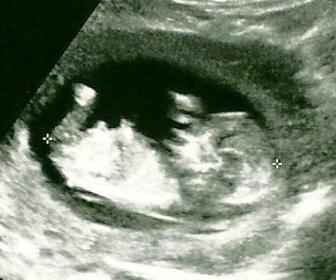

I don't think we have a nub picture here, that I can see anyhow. But I thought it might be fun to see what other members think our SIXTH baby is going off the pictures we do have. :) Thanks in advance! :)